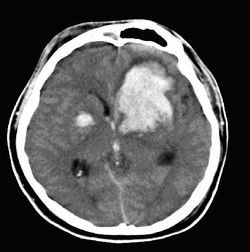

beyin kanamalarının